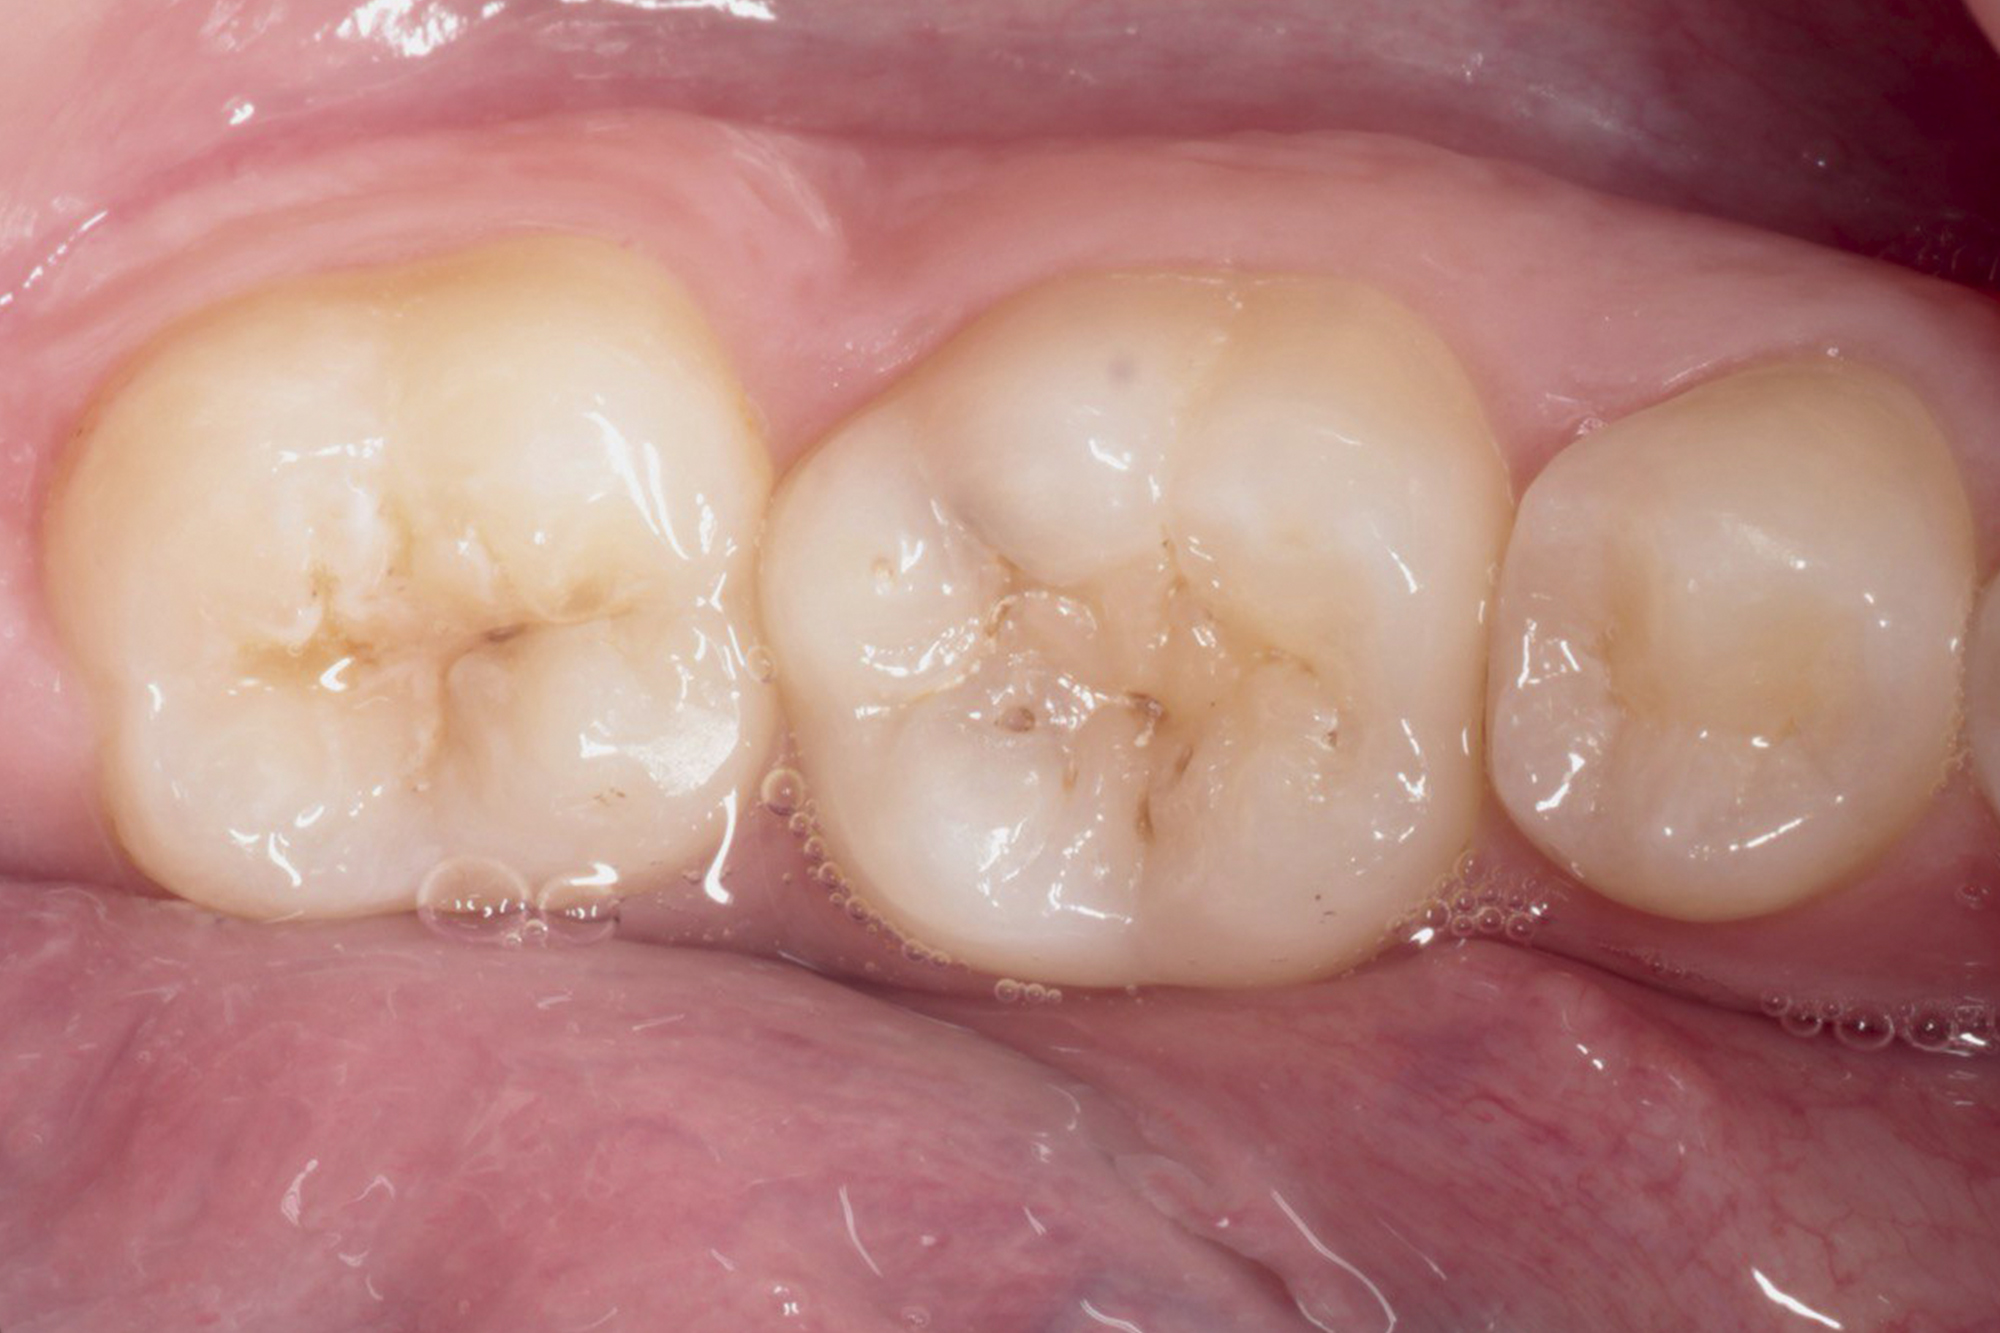

Наши работы